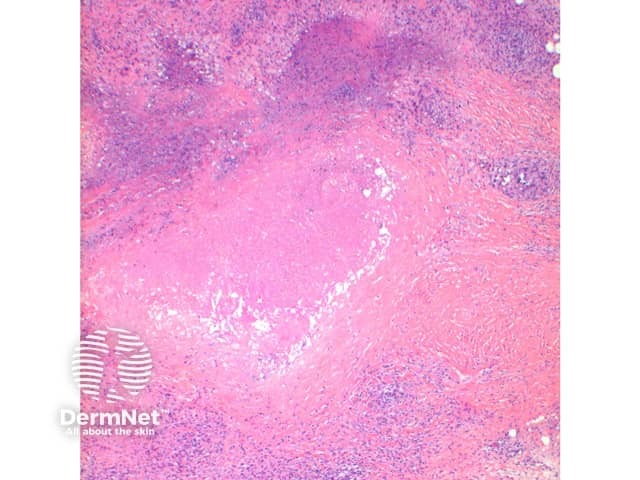

The scanning view of the histology of granuloma annulare shows a granulomatous inflammatory pattern situated within the superficial and mid dermis.

Figure 2